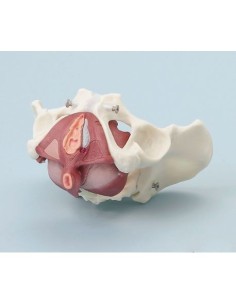

Modèle anatomique du squelette du bassin d'un homme 3B Scientific H21/1

3B Bassin scientifique, anatomique Modèle pour illustrer l'accouchement L30